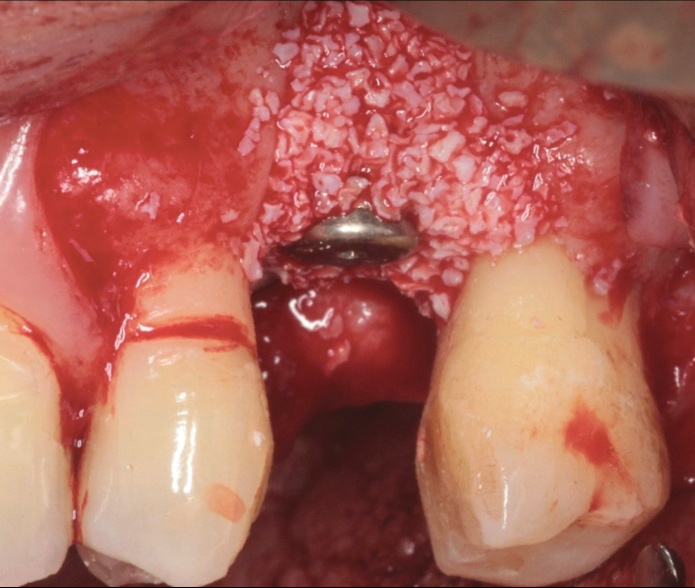

Although the goal of the treatment of peri-implantitis should be the regeneration and reconstruction of the bone loss from the disease process (Figure 20 through Figure 25), there is limited evidence from prospective case series that this outcome may be predictable when using combinations of bone replacement grafts with barrier membranes in specific anatomical bone defect configurations.28

Fig 20. Treatment of peri-implantitis: occlusal view of peri-implant three-wall defect after thorough implant debridement.

Figure 20

Fig 21. Frontal view of peri-implant three-wall defect after thorough implant debridement.

Figure 21

Fig 22. Peri-implant defect filled with a bone replacement graft.

Figure 22

Fig 23. Peri-implant defect filled with a bone replacement graft and covered with a bioabsorbable membrane.

Figure 23